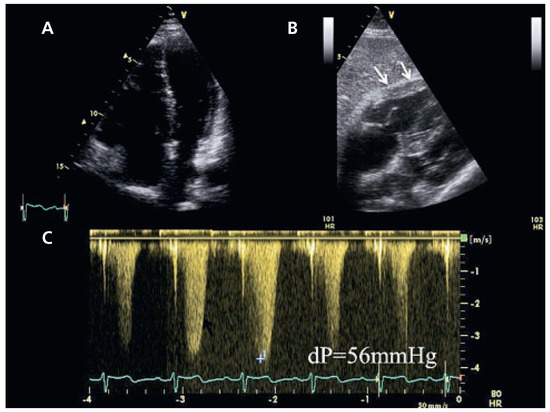

We describe the case of a 79-year-old female patient presenting with an exacerbated exertional dyspnoea. Clinical findings showed mild signs of right heart failure. Echocardiography detected right atrial and right ventricular dilatation, with moderate to severe PH and normal biventricular systolic function. There [...] Read more.

We describe the case of a 79-year-old female patient presenting with an exacerbated exertional dyspnoea. Clinical findings showed mild signs of right heart failure. Echocardiography detected right atrial and right ventricular dilatation, with moderate to severe PH and normal biventricular systolic function. There was no atrial septal defect. The patient was submitted to a thoracic CT scan for a suspicion of thrombo-embolic disease. To our surprise, this investigation demonstrated an isolated anomalous drainage of the left superior pulmonary vein into the left innominate vein. We attributed the pulmonary hypertension to the associated left to right shunt. Full article